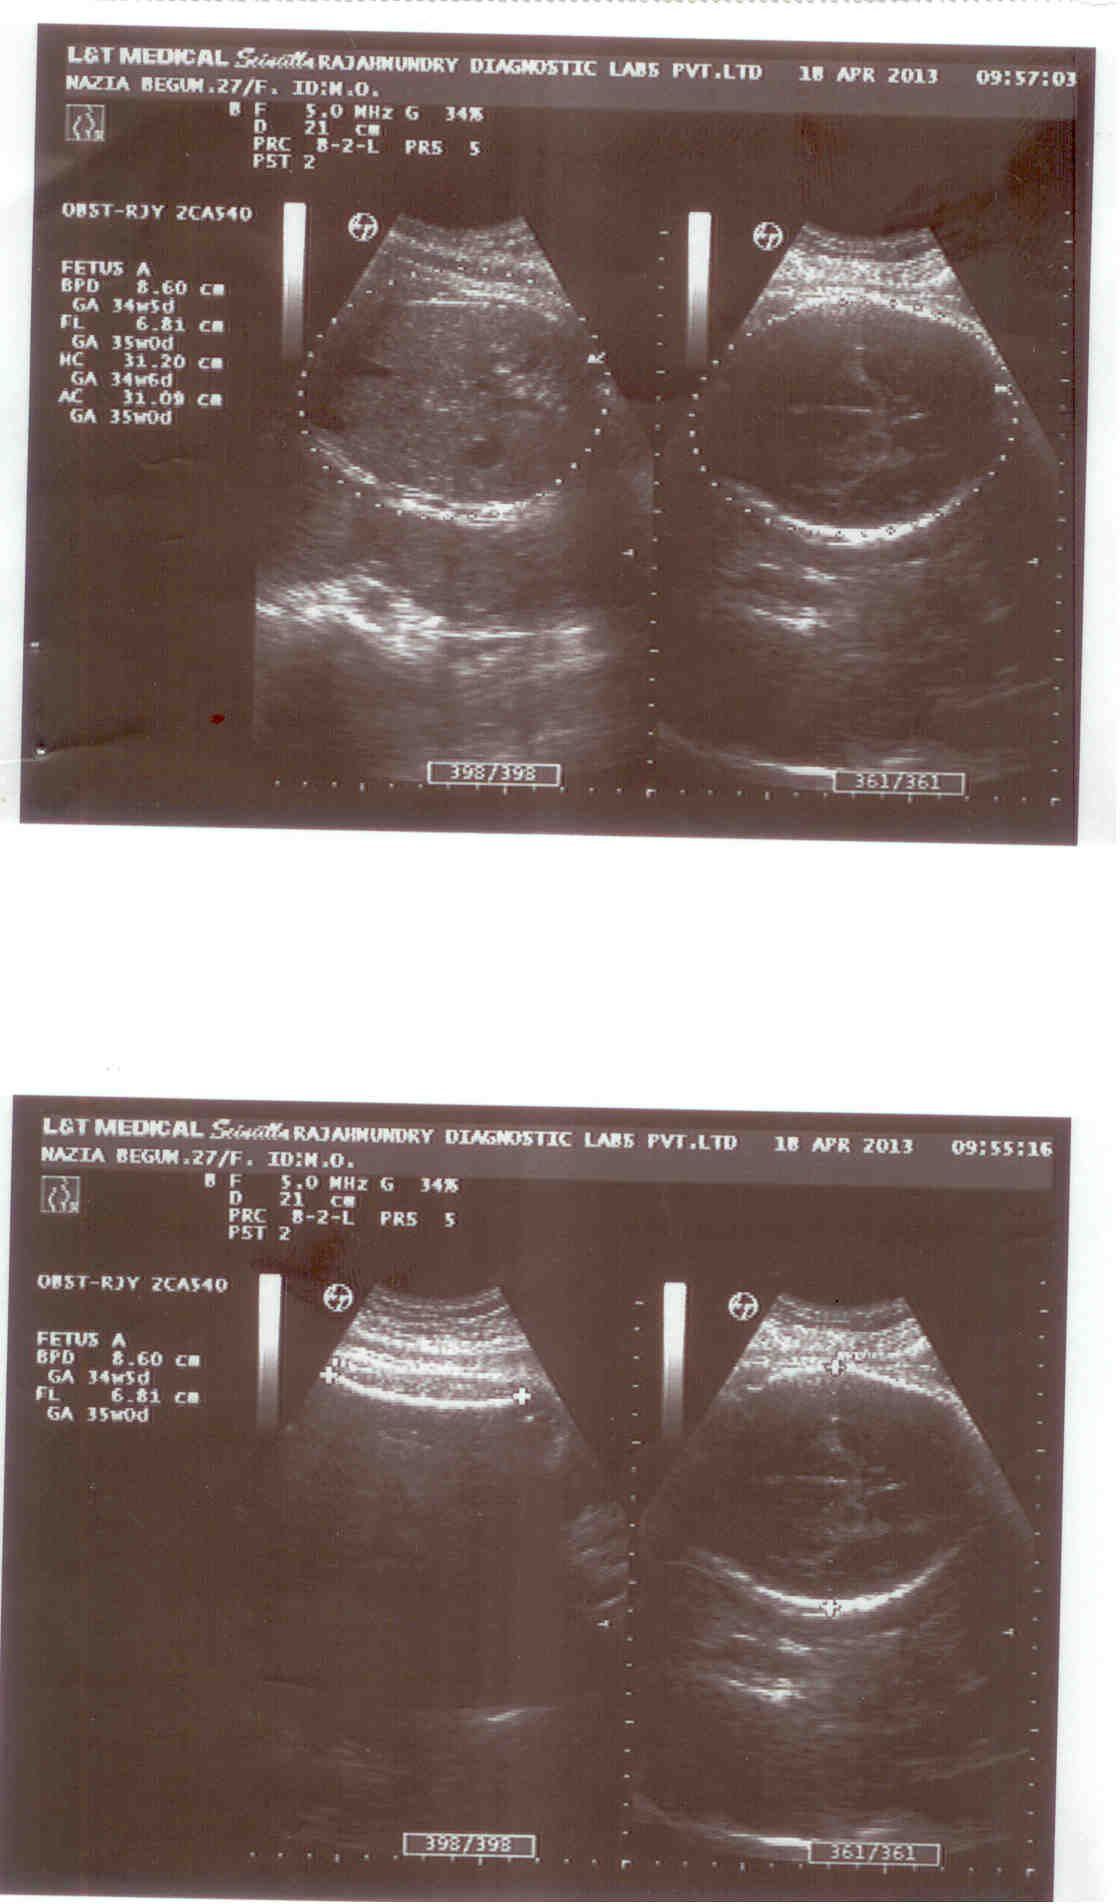

this is scan photos of my my 32 weeks baby can anybody tell or help me in getting the gender of babyAttachment 10902

I could be wrong, but I don't think there is anything there to indicate baby's gender. You need a shot of between the legs, as far as I can see that is the baby's stomach. Leg shots look like a V, where you see the bones of the 2 legs.

Are you from a country where they won't tell you gender? If so I doubt they will give you a picture of a gender shot :(